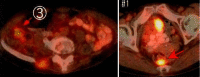

The standard treatment for colorectal mucosa-associated lymphoid tissue (MALT) lymphoma has not yet been established due to the rarity of the disease. Here, we report a case of long-term response to chemotherapy for colorectal MALT lymphoma (stage I). A 77-year-old frail female patient with diabetes mellitus and dementia developed melena of unknown etiology, and a colonoscopy was performed at a nearby hospital. A biopsy suggested malignant lymphoma, and she was referred to our department. As a result of re-examination of colonoscopy, a total of 3 submucosal tumor-like lesions were confirmed. Of these, a biopsy of the lesions in the ascending colon and rectum was performed, and MALT lymphoma was diagnosed on the basis of the histopathological findings. Following close examination, no other lymphoma lesions were found, and the patient was diagnosed with primary colorectal MALT lymphoma, stage I. After 1 course of R-THP-COP chemotherapy (rituximab + cyclophosphamide, pirarubicin, vincristine, and prednisone), the rectal lesion was confirmed to have almost disappeared endoscopically, and lymphoma cells were not found histopathologically. The patient was determined to be in complete remission (CR). However, due to hematological toxicity and a slight worsening of glucose control, the second chemotherapy course was changed to the BR regimen (rituximab + bendamustine), and 4 courses were performed (5 total courses of chemotherapy). Currently, >3 years have passed since reaching CR, and the patient is alive without recurrence.